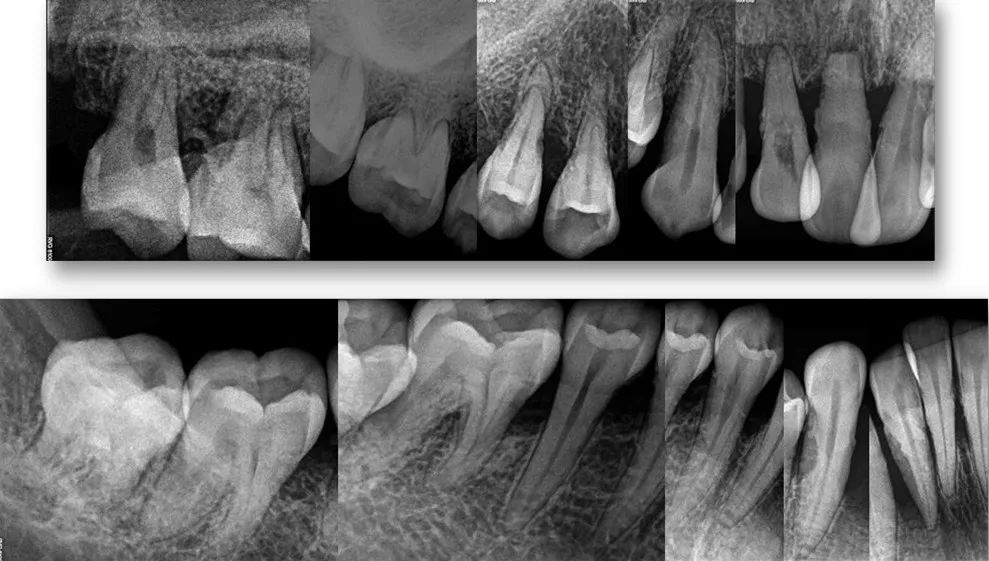

正常的牙體組織在X線片上表現為:X線阻射的牙釉質、牙本質包繞X線透射的牙髓組織,根尖周膜為X線透射區,根尖周的牙槽骨表現為密度低於牙齒硬組織的X線阻射區。通常牙體牙髓的病變表現為X線片上密度的改變。X線片檢查作為牙髓病和根尖周病基本的、必需的檢查手段,可用於每一位患者。

(1)有助於瞭解齲損的部位和範圍,以及有無繼發齲和鄰面齲;瞭解牙體發育異常,如畸形中央尖和畸形舌側窩等。

(2)可協助發現牙根的異常情況,如牙根外吸收)、根折、牙骨質增生和牙根發育不全等。

(3) 瞭解髓腔情況,如髓室、根管鈣化和牙內吸收等。

(4)用於鑒別根尖周肉芽腫、膿腫或囊腫等慢性根尖周病變。

(1)治療前可有助於擬定治療計畫,包括揭示牙根和根管的數目、大小和形態,以及根尖周病變的類型和範圍、牙周組織破壞程度等